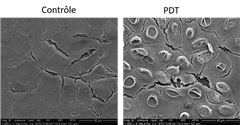

Grâce à une technique de spectroscopie originellement développée pour la science des matériaux, l’eau devient un moyen original pour suivre la réponse biologique des cellules à un stress spécifique, comme l’exposition à un agent thérapeutique photoactivable. C’est ce que viennent de mettre en évidence des scientifiques dans une étude parue dans la revue Advanced Science. Ces résultats ouvrent de nouvelles perspectives dans la compréhension de phénomènes biologiques induisant une modulation du contenu en eau de la cellule, comme c’est le cas dans le traitement anticancéreux par thérapie photodynamique.